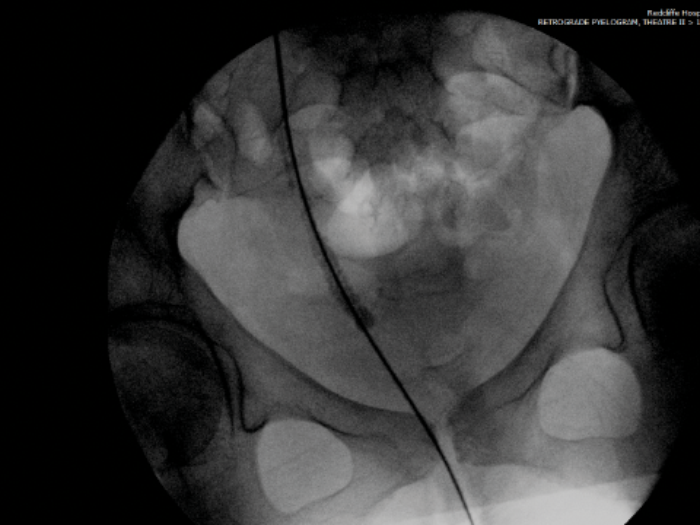

- She is taken to theatre and the intraoperative fluoroscopy is shown (Figure B). What does she have?

- Where does its name come from?

-

Right ureteric steinstrasse.

Steinstrasse is German for ‘stone street’. The term was coined by Egbert Schmiedt and Christian Chaussy, German pioneers of shockwave lithotripsy (SWL), in the 1980s. It is often seen as a complication post SWL where stone fragments block the ureter to form a ‘stone street’.